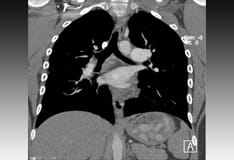

Pulmonary veno-occlusive disease in a 43-year-old man. An axial computed tomography (CT) scan (lung window level) shows multiple septal lines (arrowhead) and a dilated central pulmonary artery (arrow). Image courtesy of Thoracic Imaging Section, Department of Radiologic Pathology, Armed Forces Institute of Pathology.